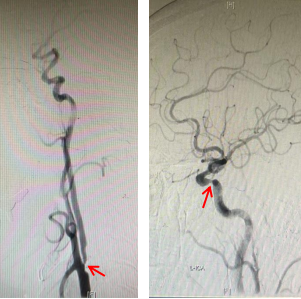

脑血管造影示右侧颈内动脉起始部极重度狭窄(左图箭头),左侧颈内动脉C4重度狭窄(右图箭头)

入院后,全脑血管造影检查提示,除已知的右侧椎动脉闭塞之外,老李还存在两处严重病变:一处是重达90%的右侧颈内动脉起始部狭窄,颈部斑块成分学检查显示存在溃疡斑块,这类斑块因内部血流动力学不稳定、反复炎症出血激发凝血机制等原因,更易导致颅内外血栓形成。另一处是左侧颈内动脉颅内段一处达70-80%的重度狭窄。